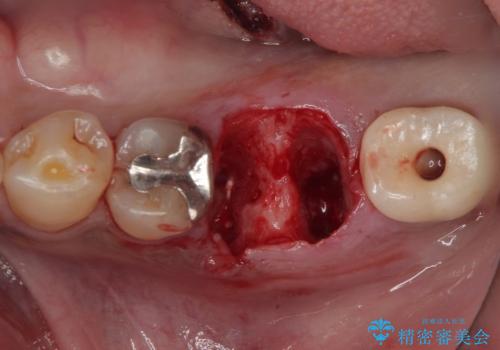

- 以前、咬合力の強さで歯の神経が失活してしまい、当院にて根管治療を行った患者様ですが、今度は咬合力の影響で歯根が破折してしまった患者様です。

歯根が破折してしまった歯は抜歯が必要となり、特に咬合力が強い方ですと、インプラント治療による治療がお勧めとなります。

咬合力の影響で歯が壊れてしまう方の場合、長期間欠損が続くと、連鎖するように他の歯が壊されてしまうリスクがあるため、抜歯即時インプラントにより、治療期間の短縮を図ることとしました。